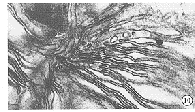

图10 对照组外节膜盘结构变形、扭曲、肿胀、空泡,呈不规则扩散 ×28000